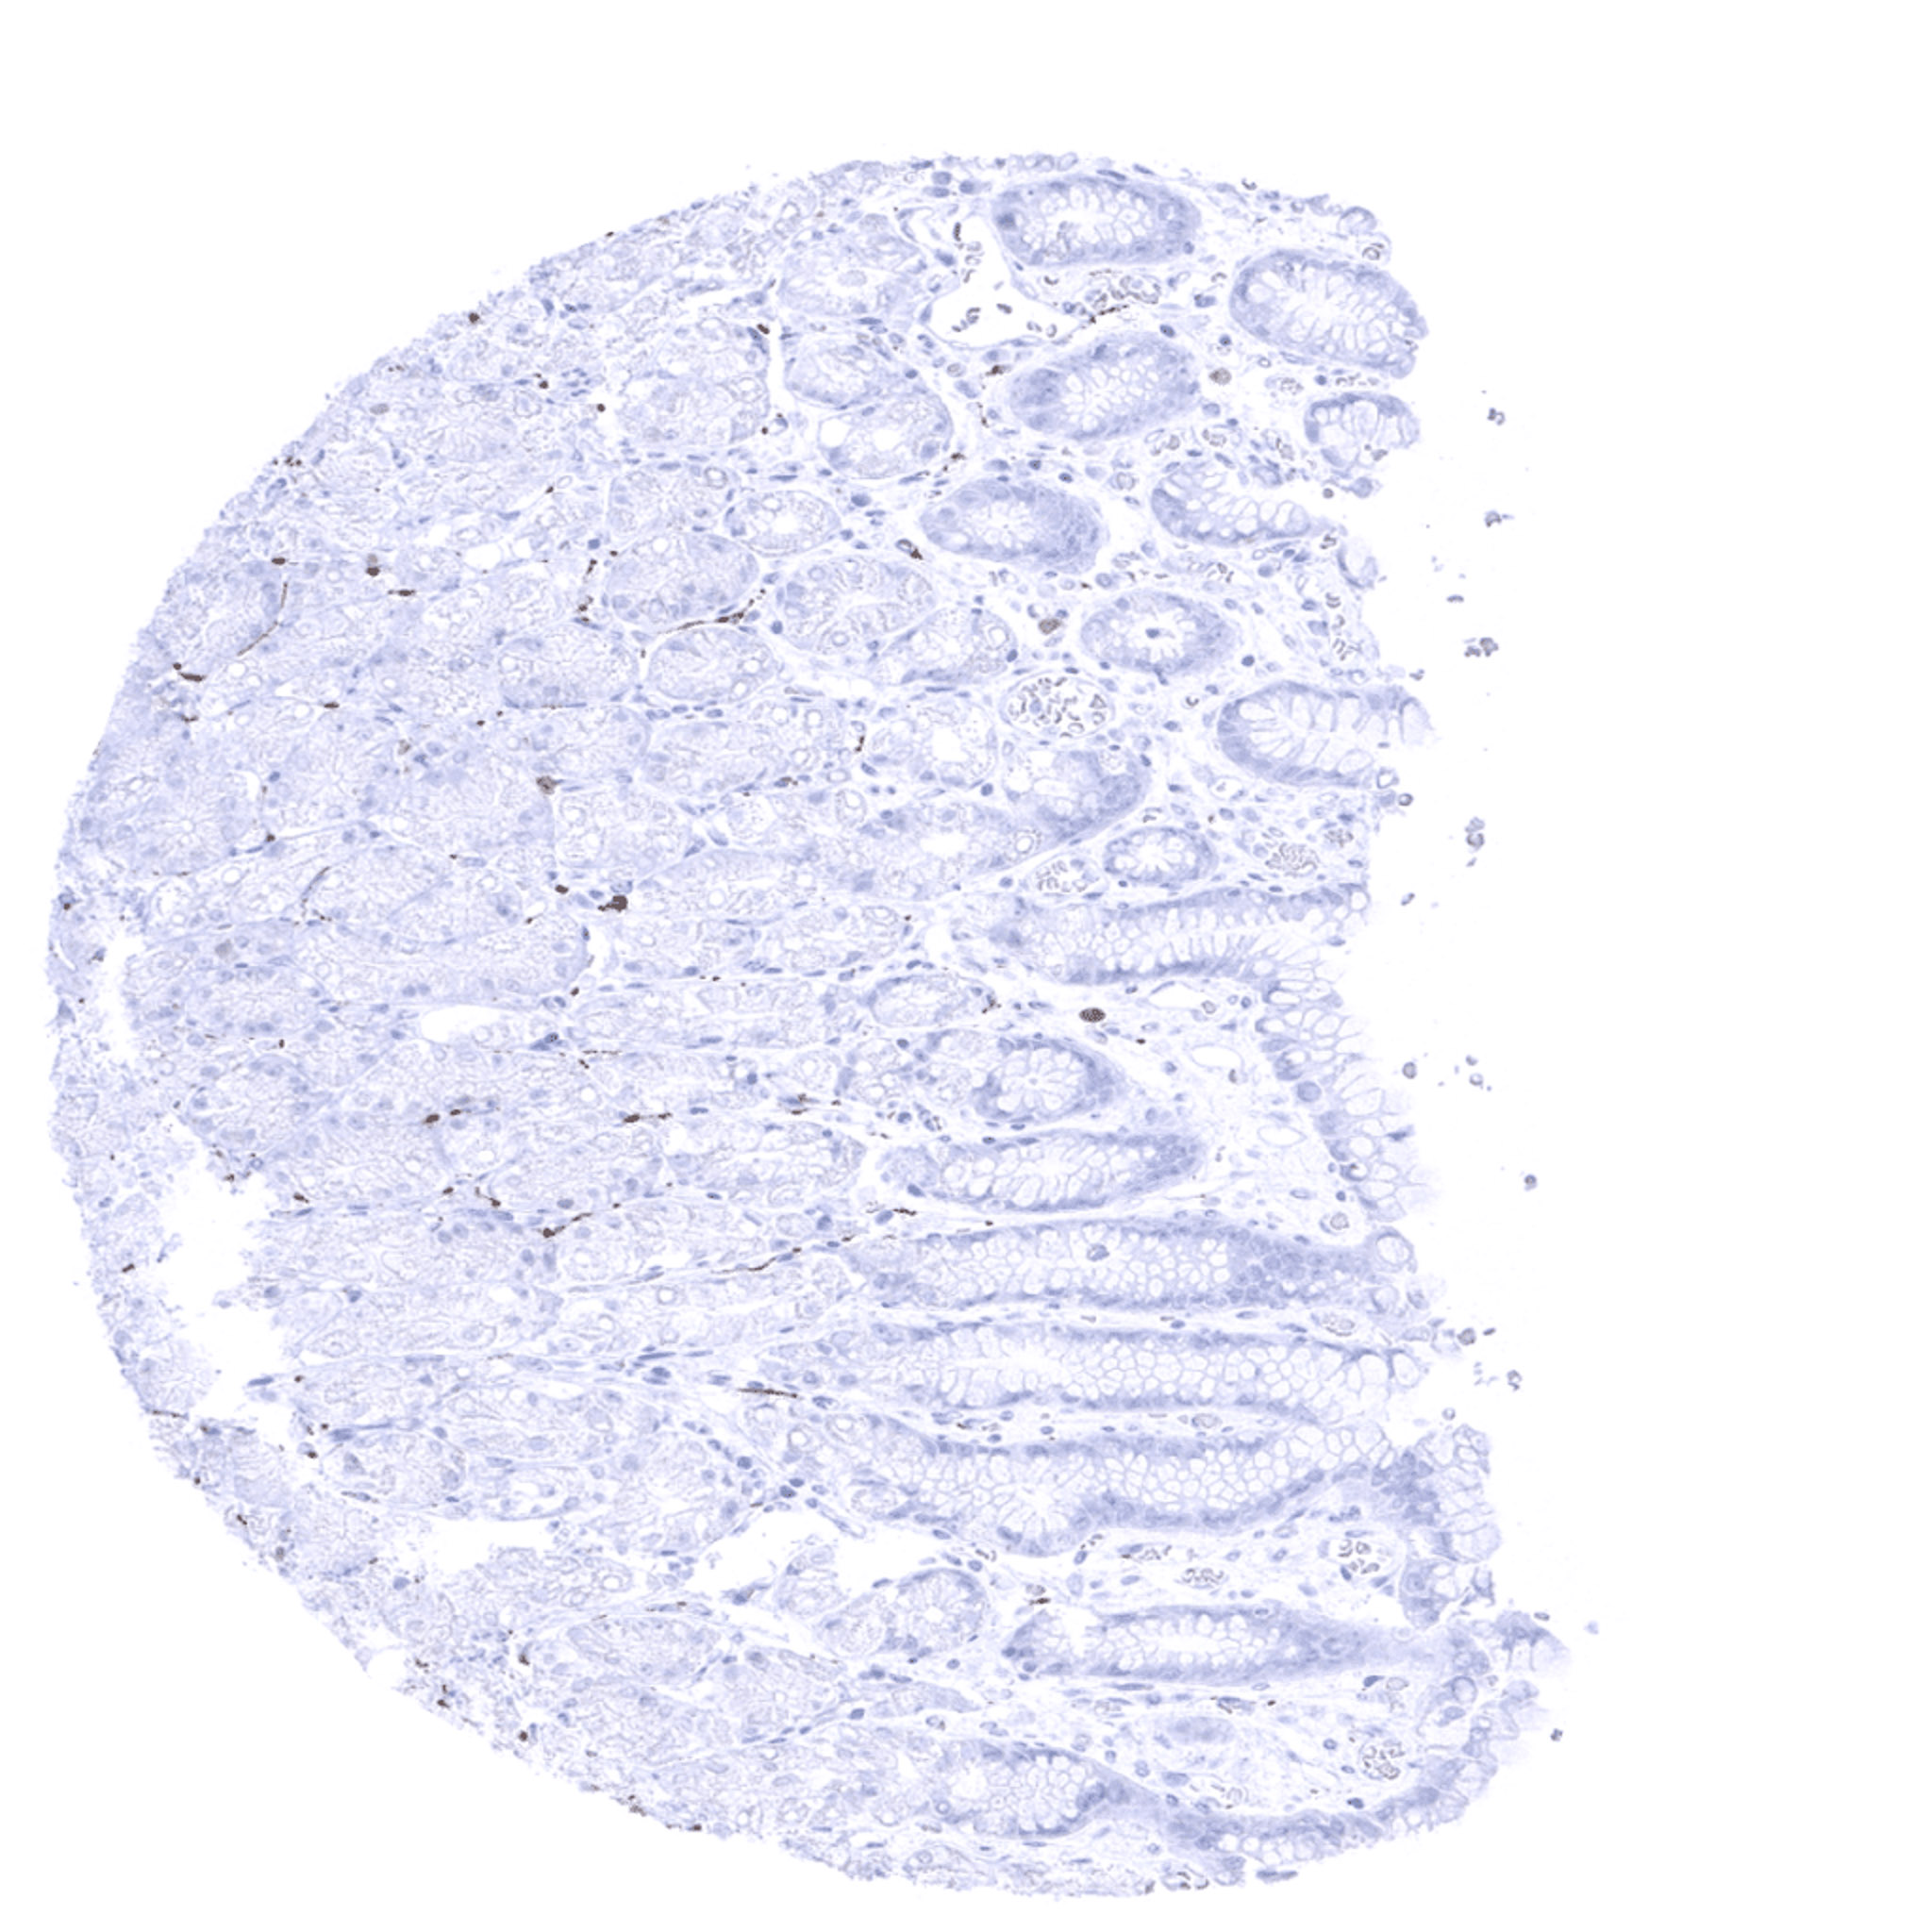

Rectum, mucosa